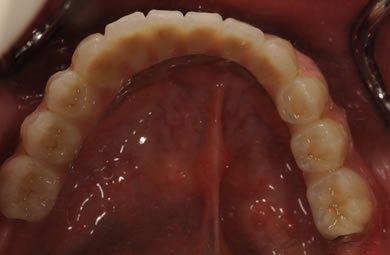

インプラントの症例写真 IMPLANT

骨再生スピードインプラント治療+AGC連結セラミック治療

| 治療内容 | インプラント12本(サイナスリフト+GBR+抜歯即日スピードインプラント+遊離歯肉移植)、AGCハイブリッドセラミック連結ブリッジ2装置(上顎・下顎)、テンポラリーインプラント2本 | ||||||||||||||||||||||||||||||||